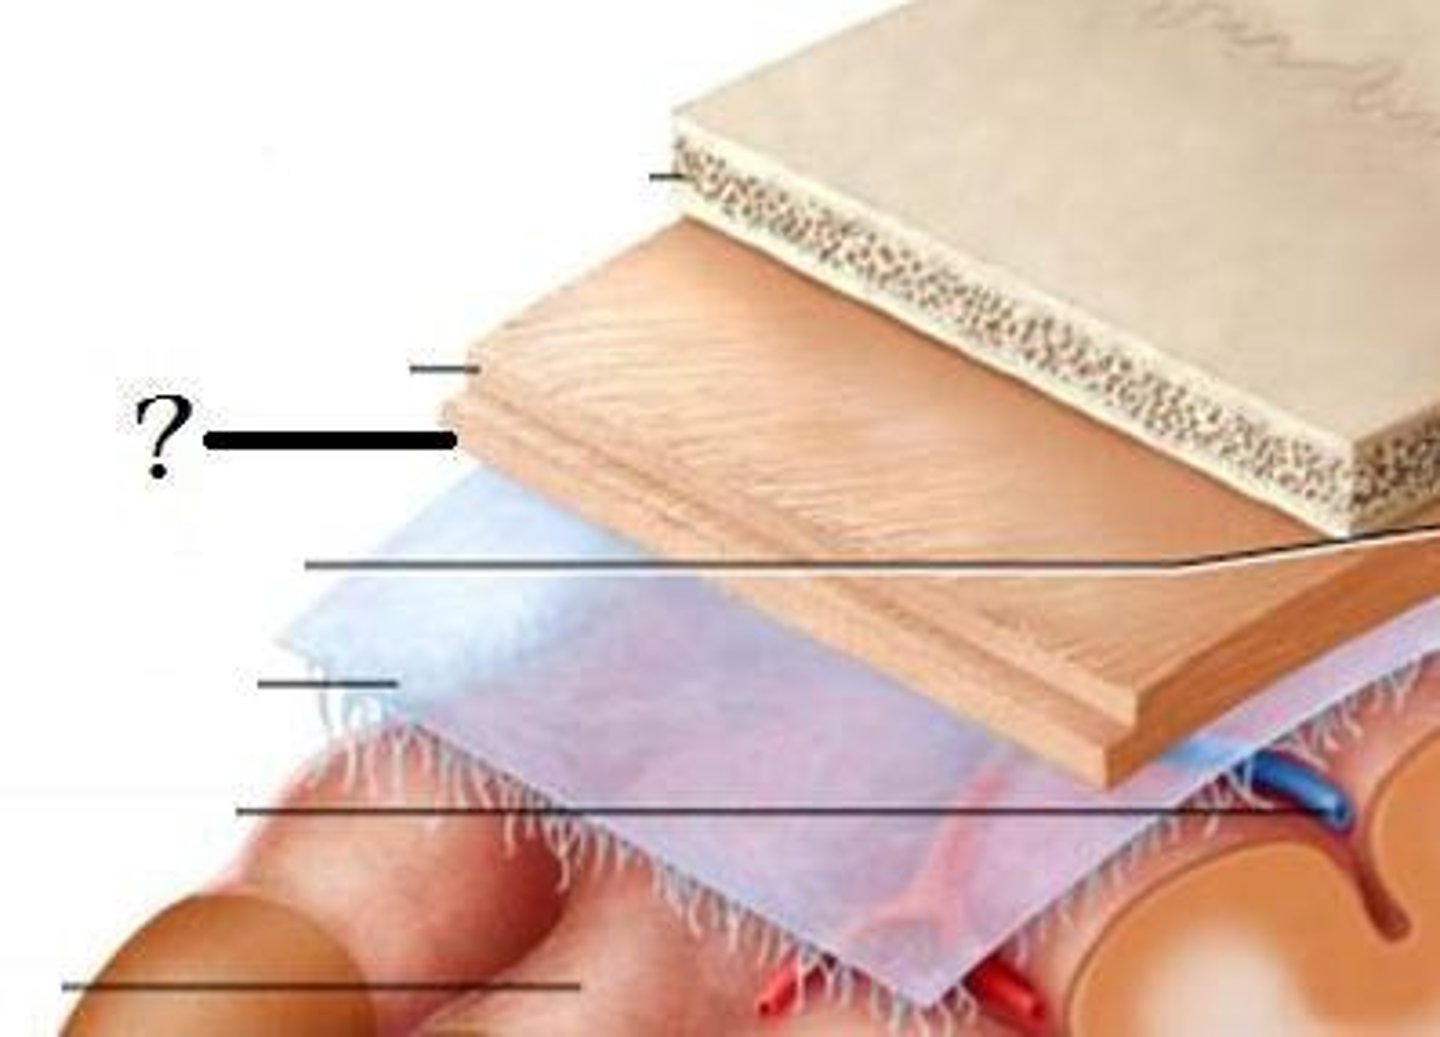

dura mater

periosteal layer

meningeal layer

arachnoid mater

subarachnoid space

with arachnoid trabeculae

pia mater